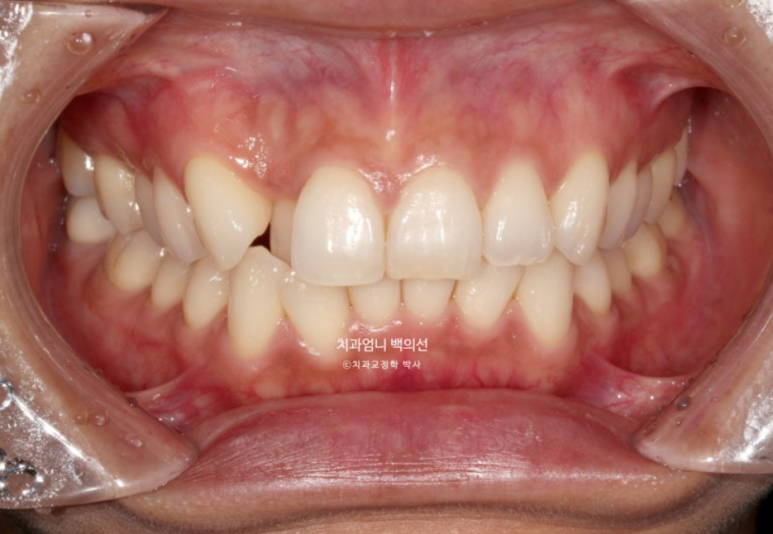

중심선은 잘 맞으나 입천장에 위치했던 축절치가 아직 완벽하게 제자리를 찾지 못했습니다.

덧니의 머리부분은 앞으로 잘 나와 있지만

교합면에서 보면 입천장에 위치했던 덧니 뿌리 부분은 아직 입천장 쪽에 위치해 있습니다.

덧니쪽으로 쏠려있던 중심선은 이제 중앙을 찾았습니다.

24년 9월부터 25년 1월까지 5개월간 추가장치를 다 낀 모습입니다.

비로소 덧니는 완벽히 제자리를 찾았지만

여전히 약 1mm 가량의 위 아래 중심선 불일치가 보여 환자분 기준 우측 가운데 앞니의 치축이 미세하게 기울어져 보입니다.